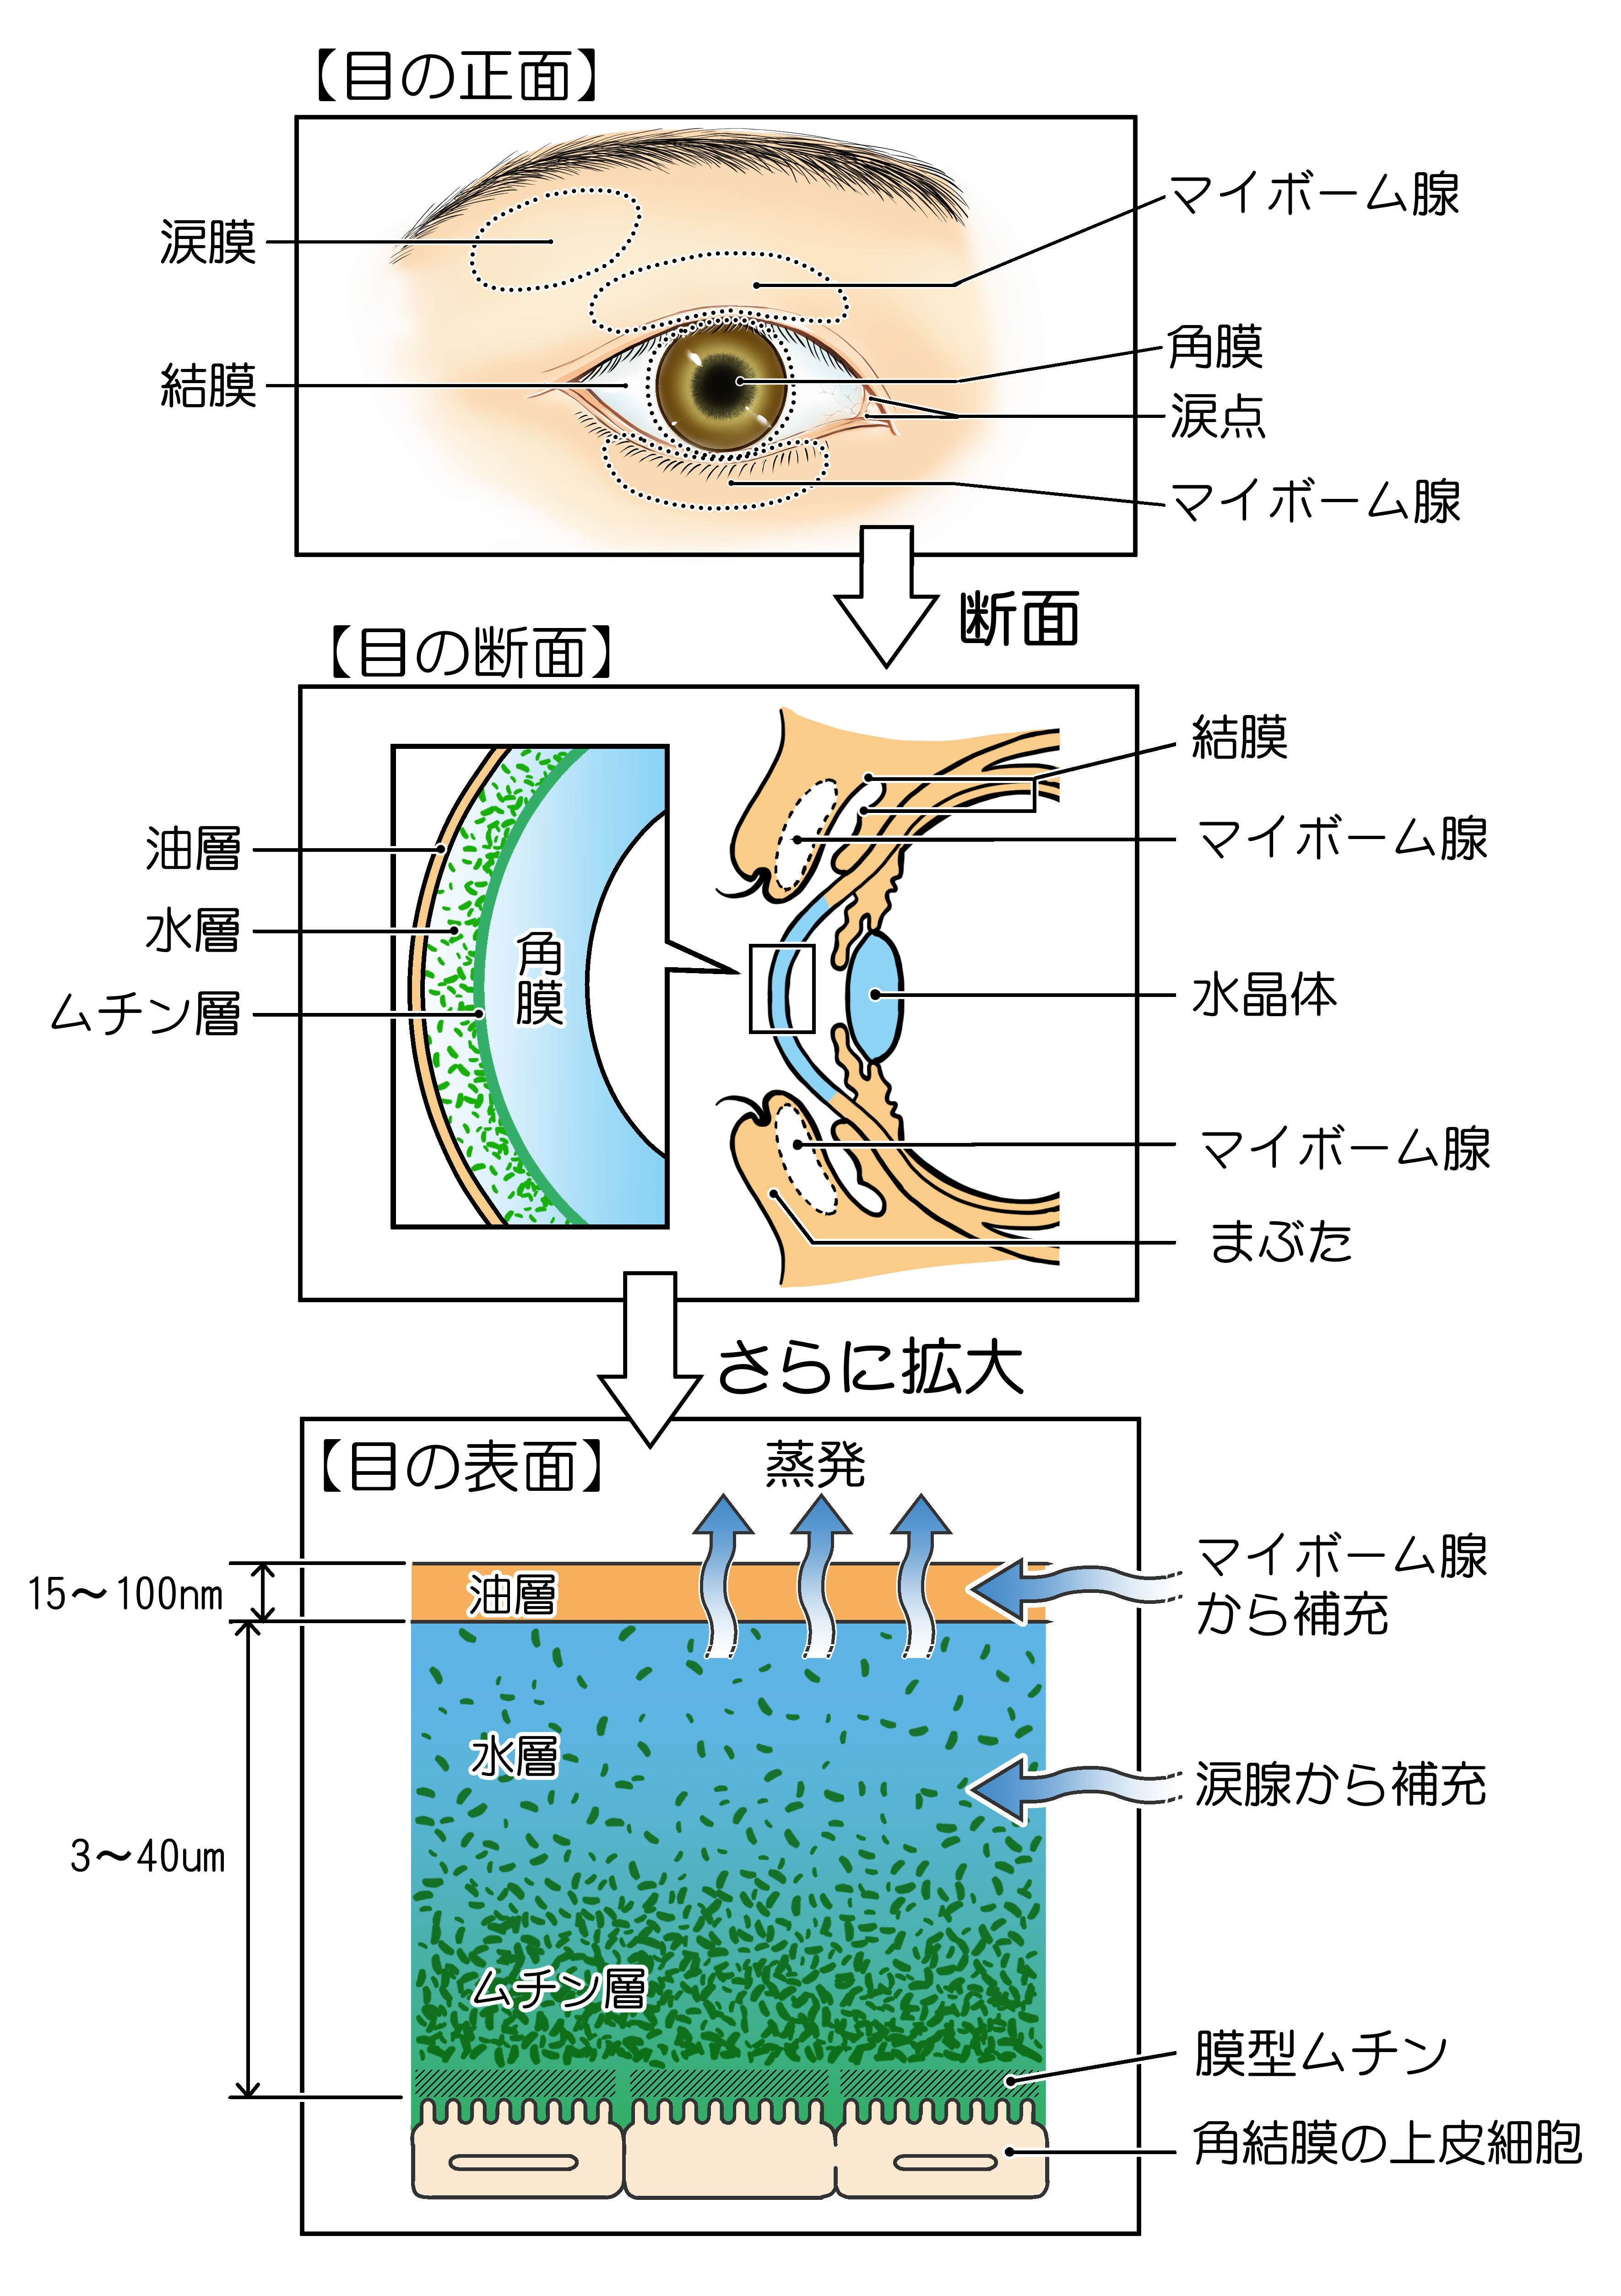

ドライアイの患者様の多くの方に

マイボーム腺の異常があることが分かりました

最近の研究ではドライアイの症状を訴える患者さんの多くの方にマイボーム腺機能不全(MGD)であることが明らかになりました。